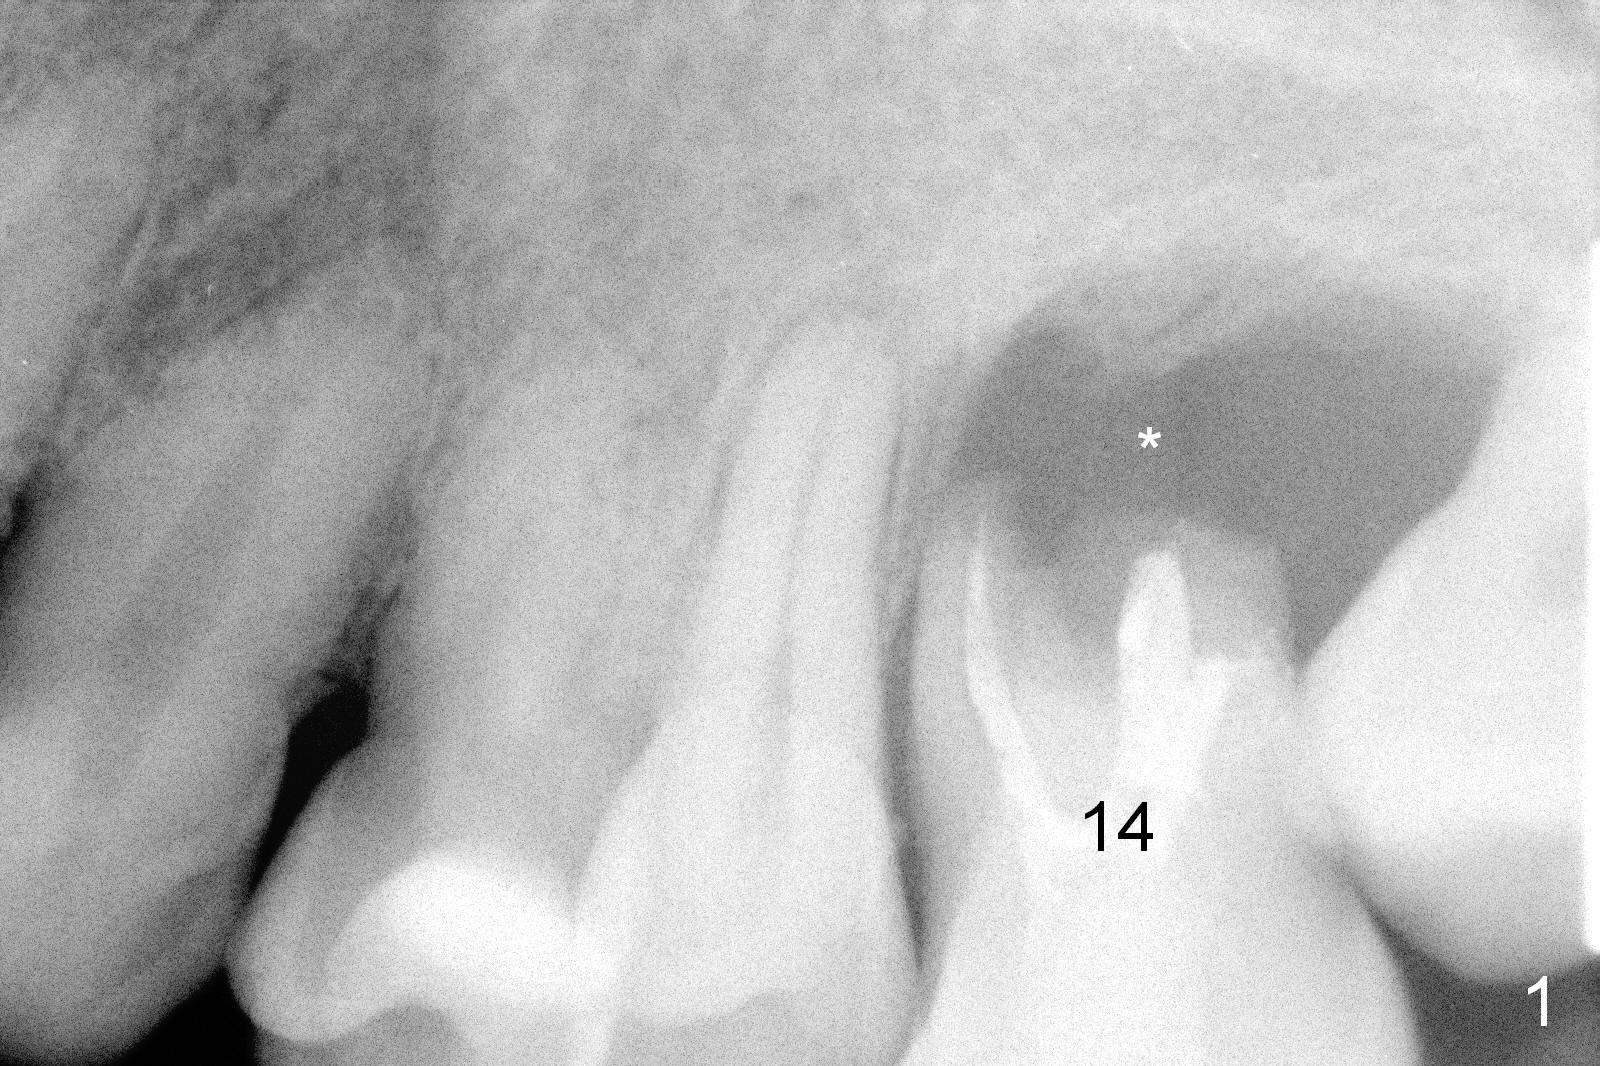

A 42-year-old man (XK) has perio-endo disease at the tooth #14. After root canal therapy (Fig.1), the tooth remains nonsalvageable. The bone loss is extensive (Fig.1 *) and uneven (more bone mesially than distally) after extraction (2% Xylocaine/1:50,000 Epinephrine). A bone-level implant is placed in an ideal depth (Fig.3 UF; Fig.4 SM), irrelevant of the gingival margin, first. Place bone graft distally (Fig.3 red circles) before choosing a proper abutment. For example, there is plenty of combination to choose cuff and abutment lengths for a SM or UF implant (Fig.4).